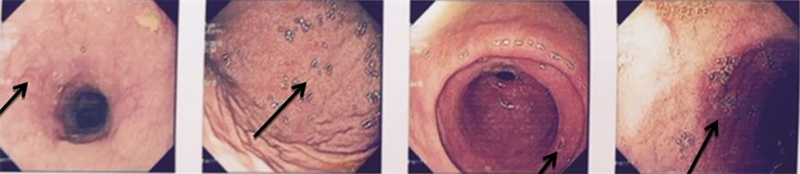

Chụp cộng hưởng từ sọ não (hình 2)

Hình 2: Hình ảnh chụp cộng hưởng từ sọ não

Kết luận: trên phim cộng hưởng từ sọ não có hình ảnh tổn thương bán cầu não (phải) kích thước 3x3,5cm, ngấm thuốc dạng viền, có nốt vệ tinh xung quanh, phù não quanh u, dấu hiệu chèn ép. Xung cộng hưởng từ phổ: tăng chuyển hóa Cholin. Kết luận: hình ảnh glioma bậc cao bán cầu não phải, kết quả sinh thiết kim xuyên sọ: glioblastoma multiform